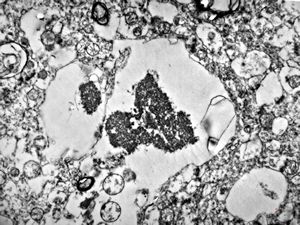

F,50y. | progressive multifocal leukoencephalopathy- viral particles in a glial cell

F,50y. | progressive multifocal leukoencephalopathy- viral particles in a glial cell

F,50y. | progressive multifocal leukoencephalopathy- viral particles in a glial cell